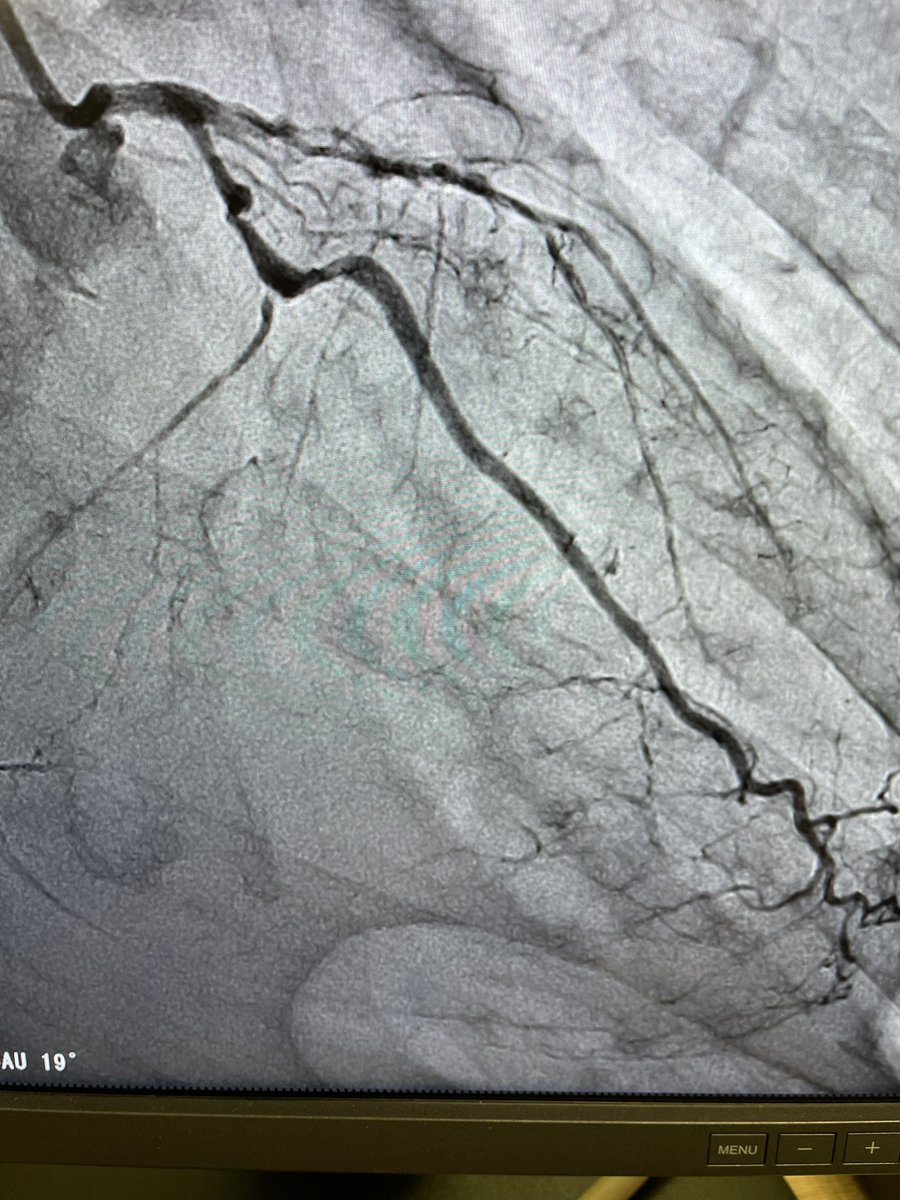

@KovacicMihajlo Agree with everyone on initial management. If decided on stent route, prepare everything for distal embolization management. Suggest no aggressive post dilation fo stent if adequate stent expansion on IVUS.